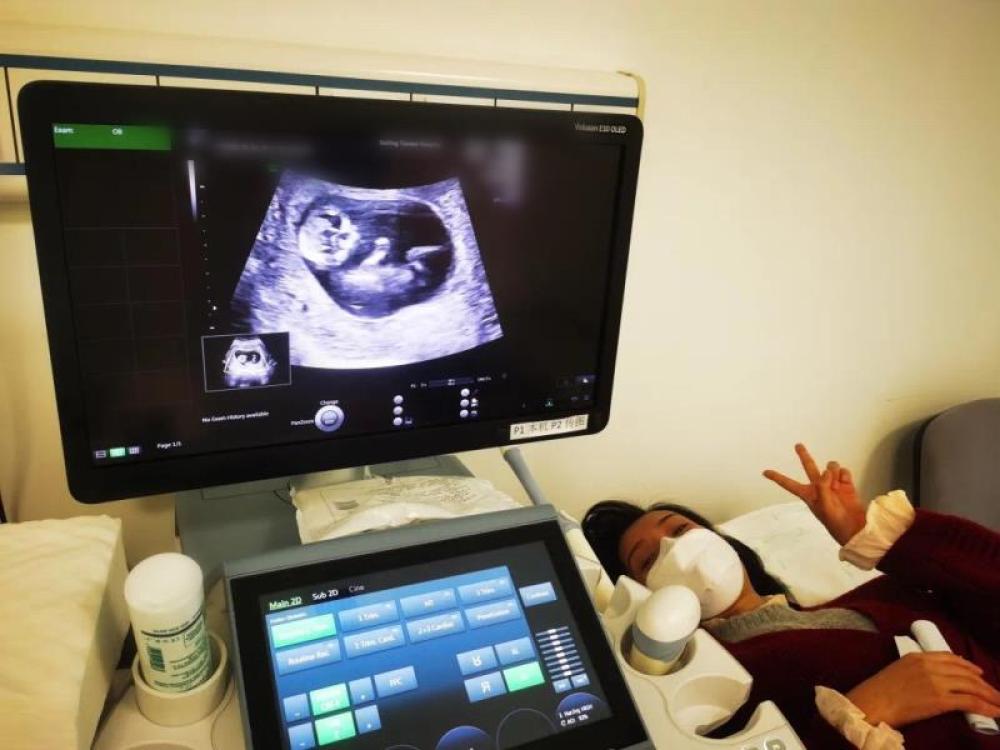

今天一早,妻子去醫(yī)院進(jìn)行B超檢查,同事用手機(jī)拍攝下了B超顯示屏上的畫面,記錄下了這個(gè)87天的小家伙第一次“亮相”。

圖為北京天壇醫(yī)院袁磊愛人做B超檢查。

“袁磊,看看你們家寶寶,可愛嗎?”收到同事發(fā)來(lái)的視頻,第一眼就看哭了,身邊的同事看完視頻也哭了。

視頻里,這個(gè)小家伙好像聽到了外面的召喚,在媽媽的肚子里伸手、踢腿、翻身,用各種動(dòng)作進(jìn)行回應(yīng)……看到他那小胳膊小腿,一種從未有過(guò)的幸福感不停地向上涌,眼淚怎么也控制不住。

其實(shí)在武漢這么多天,他一直就是我的牽掛,今天終于看到他了,那種感受真是又緊張又激動(dòng),雖然還看不清他的樣子,但是已經(jīng)感受到他的活力。